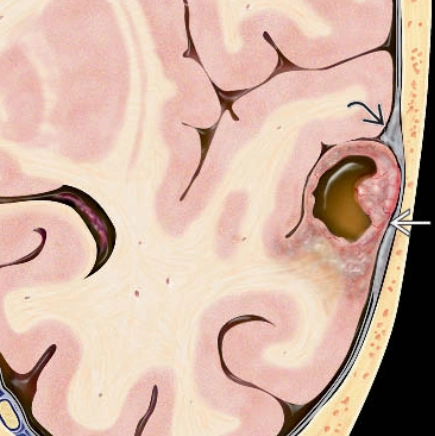

Di căn nhu mô não (Parenchymal metastases)